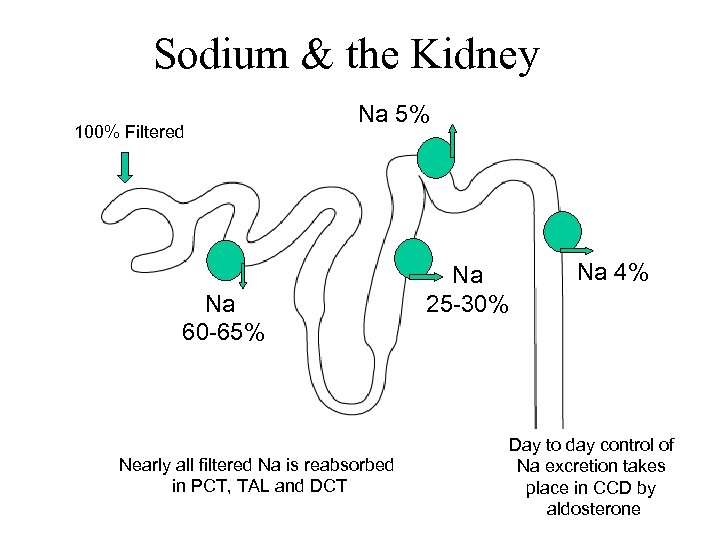

Sodium & the Kidney 100% Filtered Na 5% Na 60 -65% Nearly all filtered Na is reabsorbed in PCT, TAL and DCT Na 25 -30% Na 4% Day to day control of Na excretion takes place in CCD by aldo and ADH

Sodium & the Kidney 100% Filtered Na 5% Na 60 -65% Nearly all filtered Na is reabsorbed in PCT, TAL and DCT Na 25 -30% Na 4% Day to day control of Na excretion takes place in CCD by aldo and ADH

Sodium & the Kidney 100% Filtered Na 5% Na 60 -65% Nearly all filtered Na is reabsorbed in PCT, TAL and DCT Na 25 -30% Na 4% Day to day control of Na excretion takes place in CCD by aldosterone

Sodium & the Kidney 100% Filtered Na 5% Na 60 -65% Nearly all filtered Na is reabsorbed in PCT, TAL and DCT Na 25 -30% Na 4% Day to day control of Na excretion takes place in CCD by aldosterone